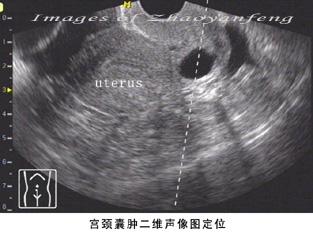

三、宫颈囊肿的图片

宫颈囊肿的图片

宫颈囊肿的B超图片